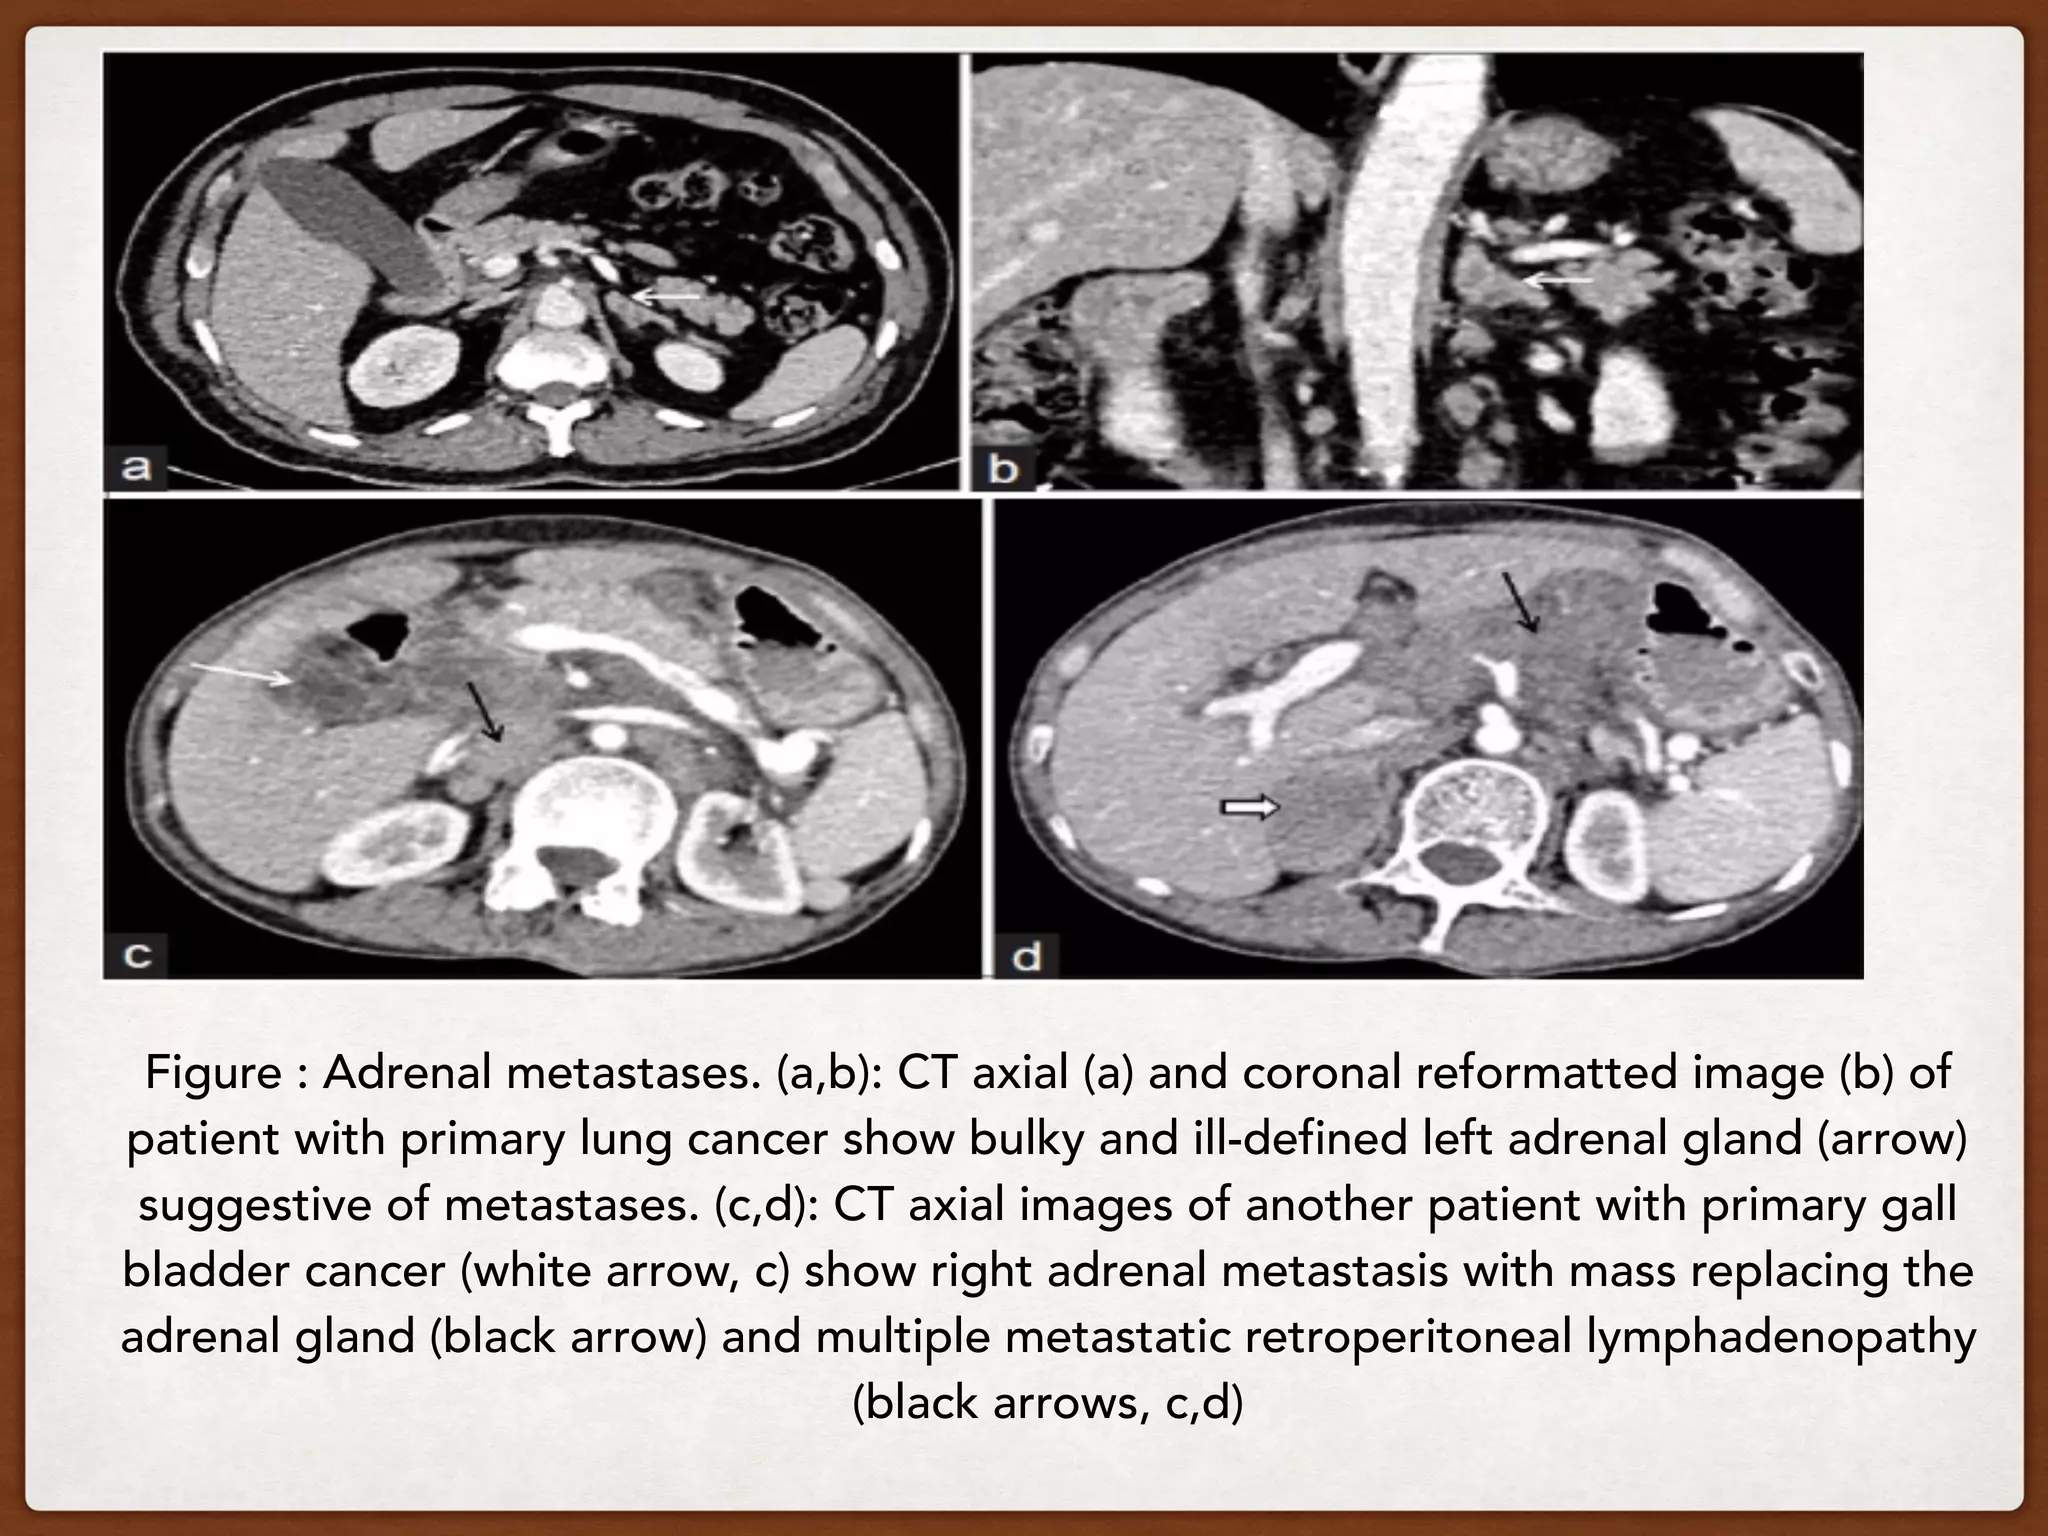

Figure : Adrenal metastases. (a,b): CT axial (a) and coronal reformatted image (b) of

patient with primary lung cancer show bulky and ill-defined left adrenal gland (arrow)

suggestive of metastases. (c,d): CT axial images of another patient with primary gall

bladder cancer (white arrow, c) show right adrenal metastasis with mass replacing the

adrenal gland (black arrow) and multiple metastatic retroperitoneal lymphadenopathy

(black arrows, c,d)